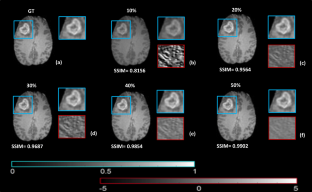

Fig. 5